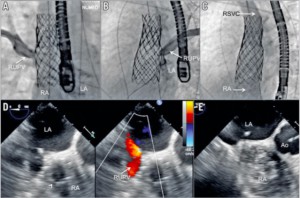

手技は全身麻酔下、経食道超音波サポート下に行います。大腿静脈穿刺でアクセスを作製し、まず心房中隔穿刺、心房中隔アプローチで右肺静脈にプロテクトワイヤーを留置します*。次に大腿静脈から上大静脈まで進めたサイジングバルーンを拡張し、血管サイズの測定と経食道エコーでの残存シャントの有無を確認します。また同時に肺静脈の造影と肺静脈内同時圧測定によりステント留置時に狭窄や閉塞をきたさないかを評価します。治療可能と判断される場合は、カバードステント(covered Cheatham-Platinum stent, NuMED社)を上大静脈から右心房上縁にかけて留置します。またステント固定不良に対してはステントの上部に追加ステントを行い対応しています(図4, 5)。

* 論文内では大動脈―左室―左房―肺静脈の逆行的アプローチの報告ですが、僧帽弁組織損傷のリスクから現在は心房中隔アプローチを行なっています